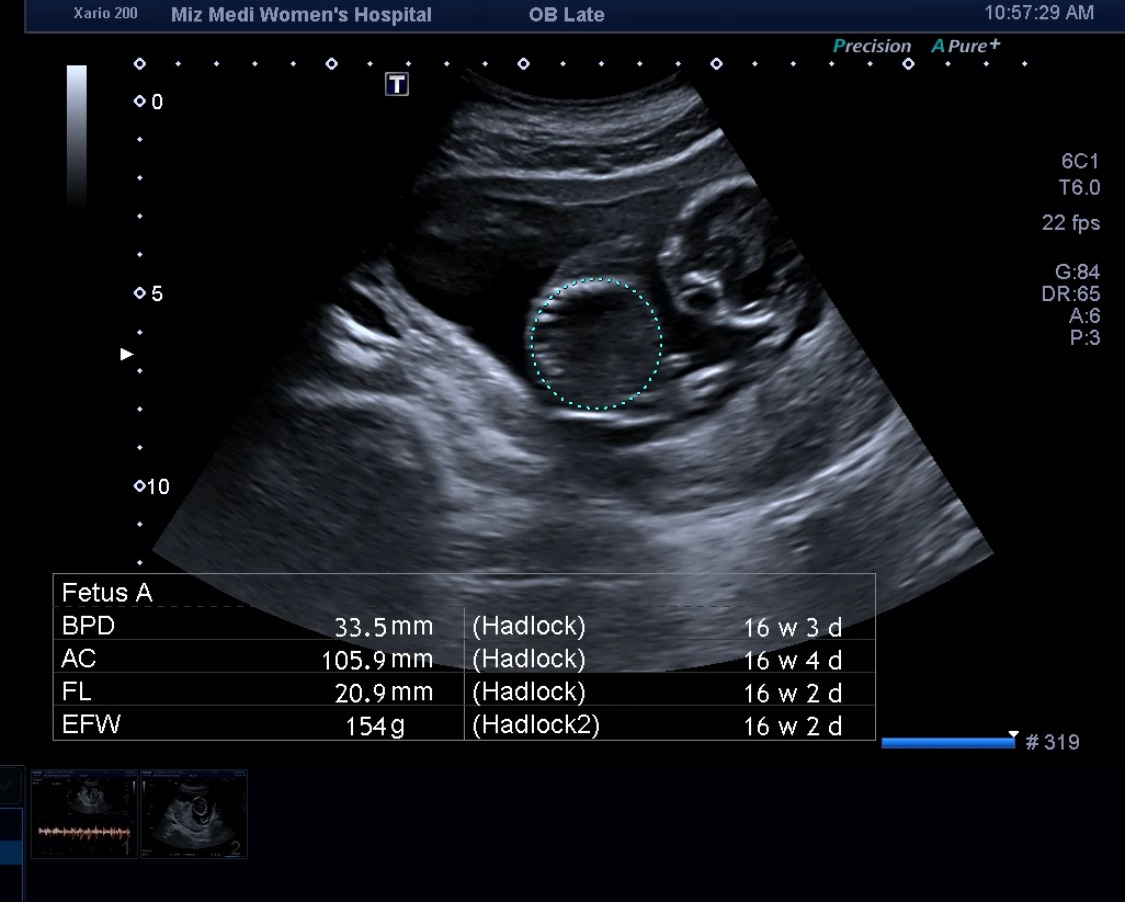

그렇게 의사 선생님께서는 머리, 다리, 팔, 배, 등 하나하나 봐주시면서 사이즈를 재주 시기 시작했다.

16주차 복부둘레.jpg

다올이 첫 신체사이즈 측정

16주차 신체 사이즈들.jpg

그리고 최종적으로 이렇게 신체사이즈를 알려준다.

해당 사진을 통해 어플에 넣으면 된다.